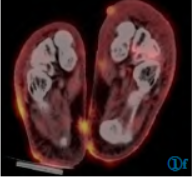

18F-FDG剂量为6.73mCi,注射后1h检查。PET/CT图像采集包括CT平扫和PET扫描。CT扫描参数:电压120keV,电流自动毫安秒,螺距0.6,层厚5mm。PET扫描,2min/床位。扫描范围颅顶至足底。图像采用CT扫描数据衰减矫正,图像重建采用有序子集最大期望迭代法。18F-FDGPET/CT显像示双肺见多发不规则结节,沿肺纹理分布,最大约10mm×15mm,轻度代谢增高,SUVmax为1.9,气管血管旁间质增厚;双下肢皮肤多发不规则结节状增厚,双足多见,代谢异常增高,SUVmax为8.0,伴双下肢水肿(图1)。

图1 18F-FDGPET/CT显像图。图1a,1b为体部及下肢MIP图,下肢见多发异常高代谢结节;图1c,1d见双肺多发结节,大部分形态不规则,沿肺纹理分布,轻度代谢;图1e,1f见双足皮肤多发不规则、结节状增厚,代谢异常增高。